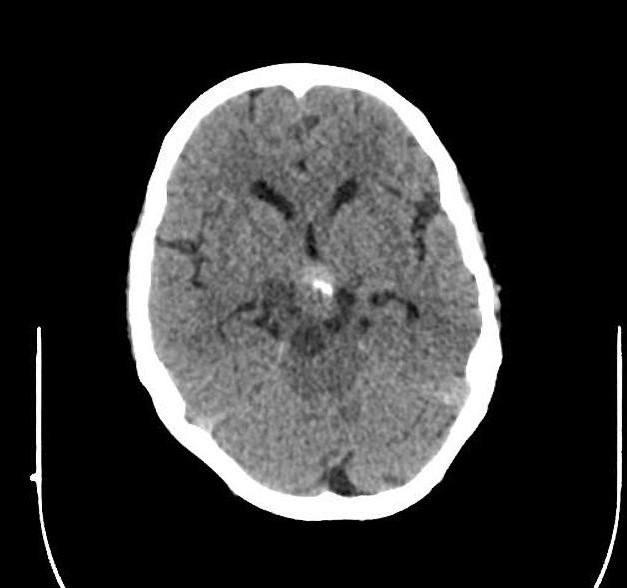

U sọ hầu

» Thông tin: Nam giới – 30 tuổi.

» Lâm sàng: Đau đầu.